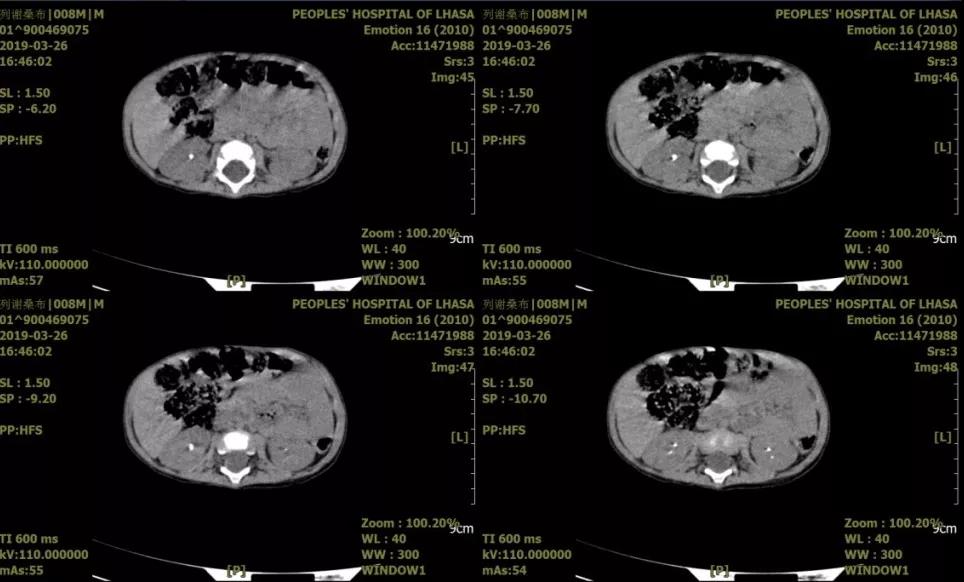

患儿,男,8月龄,主因“排尿困难伴哭闹1日”就诊。术前诊断:双肾结石;予以右侧mPCNL。

小儿肾结石病历02

患儿,男,1岁10个月,主因“腹痛腹胀伴排尿困难1天”就诊。术前诊断:1.尿道结石;2.右输尿管结石;3.双肾结石。急诊一期予以经由尿道结石碎石术+右输尿管结石碎石术+双侧输尿管结石支架置入术。二期行mPCNL。

小儿肾结石病历03

患儿,女,5岁,主因“右侧腰部疼痛1天”就诊,术前诊断:1.右输尿管结石,2.右肾结石。入院后决定一期行输尿管支架植入术,二期行mPCNL